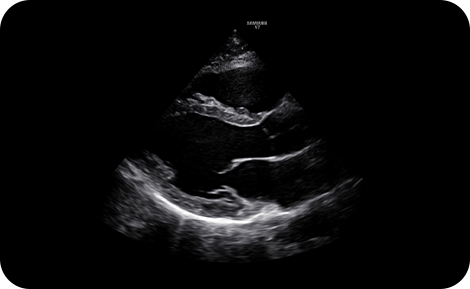

Una calidad de imagen extraordinaria

Obtenga información sobre problemas complejos con la calidad de imagen y resolución excepcionales del motor de imagen principal de Samsung, Crystal Architecture™ . La tecnología patentada combina el procesamiento de imágenes 2D mejorado y el procesamiento de señales de color detallado para optimizar y refinar la imagen.

Crystal Architecture™ empodera a los profesionales de la salud con confianza en el diagnóstico en los exámenes diarios, lo que ayuda a que se enfoquen en los pacientes individuales y no en la manipulación excesiva del sistema.